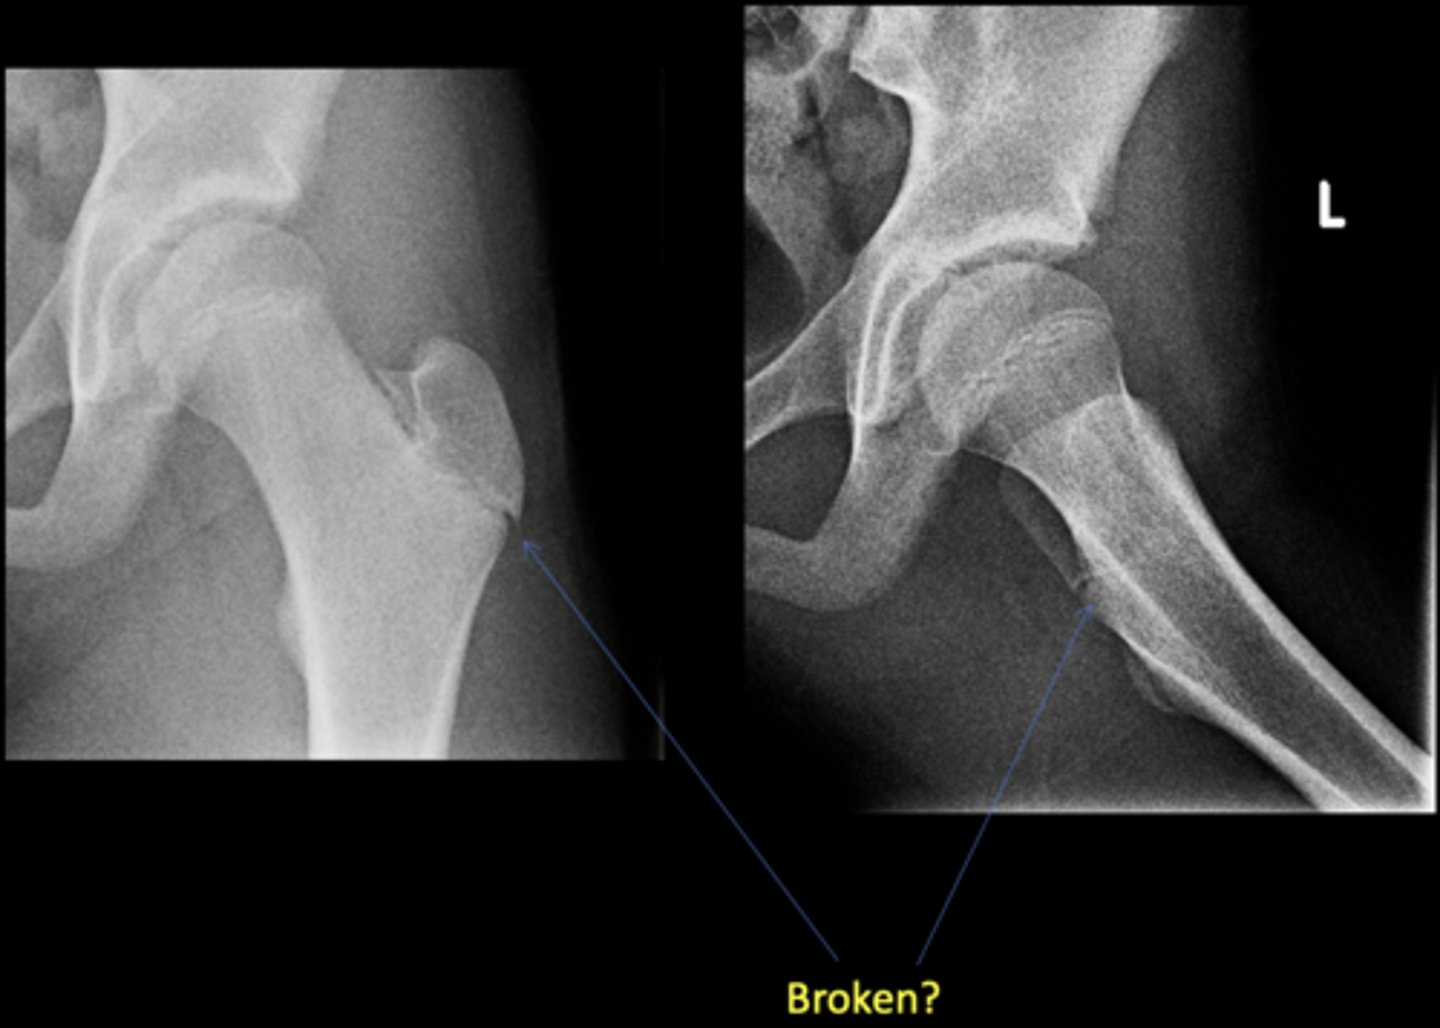

No - growth plate in a child

Broken?

<p>Broken?</p>

AP hip

View on left?

<p>View on left?</p>

Frog-leg hip

View on right?

<p>View on right?</p>